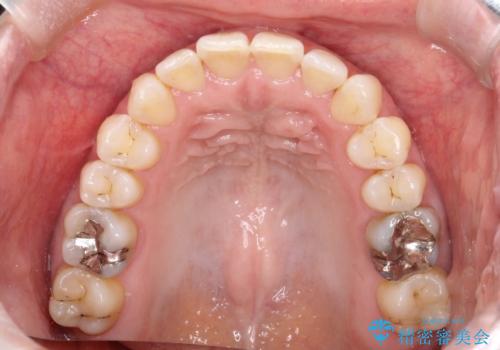

インビザラインにて治療することとしました。

内側に引っ込んでいる歯も、インビザラインにてしっかり外側に動かすことができます。